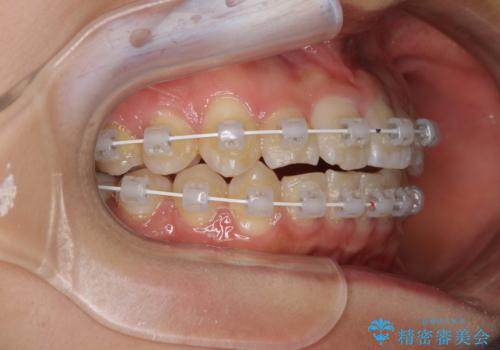

- 審美装置

- 1年

- 10-30回

お住まいが遠方であったため、マウスピースによる矯正治療も提案しましたが、ご自身でのマウスピースの管理の面倒くささと、なるべく早く治療を終えたいとのことで、ワイヤー矯正を選択されました。